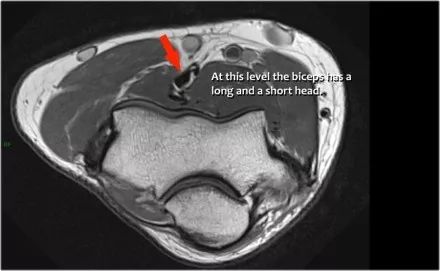

二头肌腱:从肌腱连接处到径向结节上的附着物。

远端肱二头肌肌腱的病理学很像跟腱的病理学。可以有退变,部分撕裂和完全撕裂带或不回缩。以下是73岁男性的超声图像,他们在举起一个盒子时经历了突然的疼痛和撕裂的感觉。在肘关节前方有前旋和旋后疼痛,前方有压痛。

没有瘀斑或可触及的肿块。在矢状图像上,肌腱变厚,但远端肌腱丢失。

在矢状图像上,看起来肌腱完全是刺,但继续下一个图像。

● 远端肱二头肌肌腱撕裂:有完全撕裂,因为如果我们一直跟随肌腱进入桡骨结节,我们可以看到肌腱不附着在那里(绿色箭头)。只有流体。● 肌腱不缩回的原因是因为广泛的萎缩性肌腱 - 也被称为lacertus fibrosus - 仍然完好无损(红色箭头)。● 远端肱二头肌肌腱不仅插入到桡骨结节,而且还通过褶皱纤维进入前臂内侧屈肌旋前肌块的筋膜。

当腱膜也thorn时,肌腱缩回,并且由于收缩的二头肌造成手臂明显肿胀。远端二头肌肌腱撕裂是一种罕见的损伤。大约有5%的肱二头肌受伤。这是肘部弯曲时手臂突然伸展的结果。近端肱二头肌腱撕裂更常见。通常是二头肌的长头完全撕裂。

下面这是另一个例子。在T1W图像上有一些增厚和一些中间信号。这可能是肌腱变性,但总是看T2W图像寻找撕裂。在这种情况下,有部分撕裂。

下面是另一种情况。在矢状图像上,我们不确定可能的撕裂。也许只有一些肌腱炎或肌腱炎。轴向图像显示部分撕裂(红色箭头)。

始终确保你的轴向扫描一直到结节,因为你太早停止,就像在这种情况下,你只会看到增厚的肌腱和一些液体,但你不确定可能的撕裂。